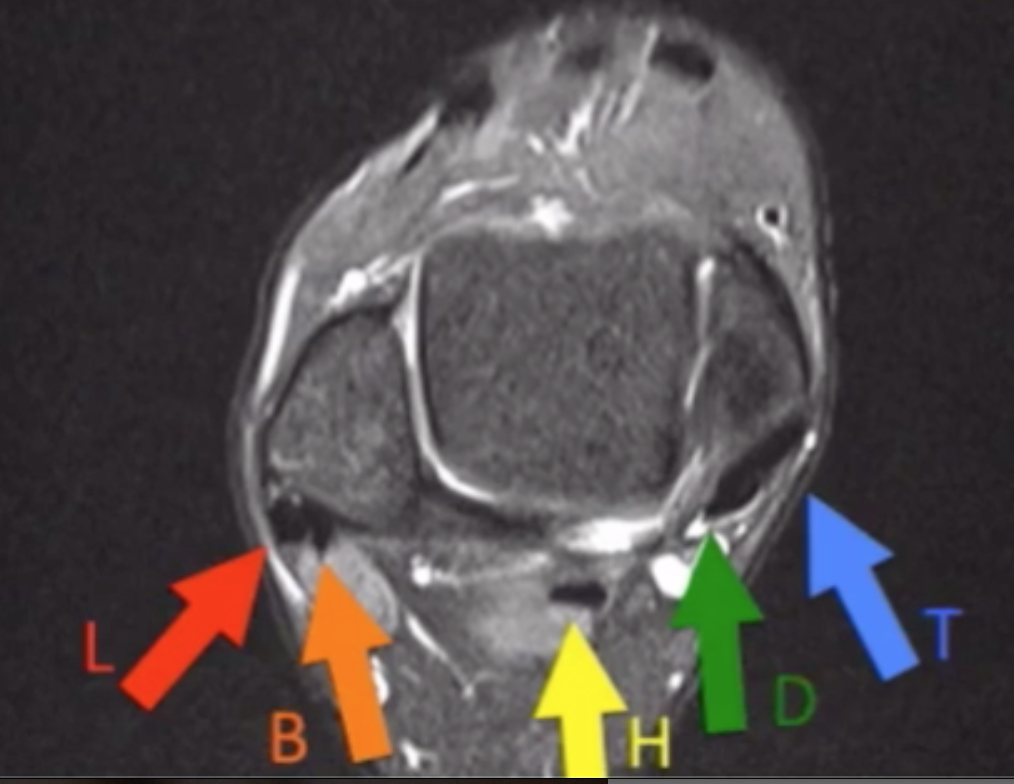

L = Peroneus longus (L = lateral)

B = Peroneus brevis

Tom - Dick - Harry

H = Hallucis

D = Digitorum

T = Posterior tibia